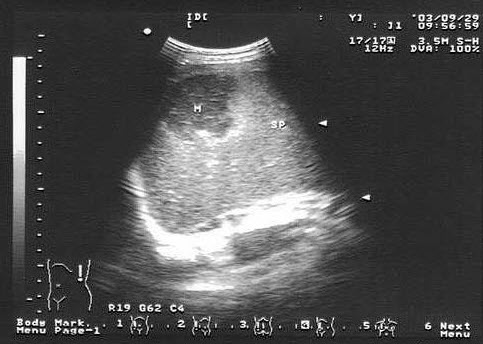

下图为宫内孕囊声像图,可见心管搏动,该胎儿至少大于多少周()

A.6周

B.9周

C.10周

D.12周

E.8周